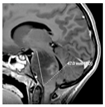

In vitro modeling of cell dissemination from hypoxic PDCL spheroids to recapitulate tumor progression in a patient. (a) Phase-contrast images and HIF-1α expression of BT68 NS in normoxic and hypoxic conditions at the indicated times. (b) Significant differential expression of seven genes involved in the hypoxia signaling pathway in cells exposed to 21% O2 versus 1% O2. (c) Diagram depicting a model of the cell dissemination from hypoxic spheroids and the immunofluorescent staining of HIFs and SOX2 (SRY-Box2) in the core and the periphery of the spheroid. (d) Quantification of the number of migrating cells. (e) Phase-contrast micrographs of PDCL migration following crystal violet staining. (f) Injected T1-weighted magnetic resonance images of patient tumors at relapse. Red arrows—distant metastasis. **** p < 0.0001; * p < 0.05. Scalebar—200 µm. DAPI: 4′,6-diamidino-2-phénylindole.

To understand the invasiveness of PDCLs in the hypoxic brain environment, we developed a spheroid in vitro model (Figure 3c) recapitulating hypoxia observed in patient brain tumors. Because the oxygen diffusion ranged from 70 µm to 200 µm in tumors and normal tissue, respectively [21], we generated spheroids (from early passages (<10) of paired MNL and NS lines) with diameters above 200 µm to create a hypoxic gradient from the periphery to the core and expanded them at 5% O2. We showed that the expression of the stem cell marker SOX2 was restricted to the periphery of the spheroid, while HIF-1α was expressed from the core to the periphery of the spheroid. We confirmed the co-expression of HIF-2α/HIF-1α and SOX2 observed in HGGs (Figure 3c). Furthermore, previous studies, comparing gene expressions in HGGs versus normal brain parenchyma, identified the extracellular matrix protein fibronectin as one of the most over-expressed gene in HGGs [22]. Then, to more carefully recreate the biology of the patient’s tumors, we immobilized the spheroids onto a fibronectin coating. The quantification of cells evading from the spheroid and the distance of migration showed that cell dissemination was slower in MNL than in their corresponding NS lines (Figure 3d). In addition, the invasiveness of each patient tumor during its progression or relapse was comparable to the migration profiles in MNL- and NS-derived spheroids (Figure 3e). As shown on MRI, the highly diffusive BT69 tumor relapse in the left thalamic initial site and in the contralateral anterior ventricle was similar to the highly invasive profile of the BT69 spheroid (Figure 3e,f). The localized BT83 tumor at relapse was comparable to the low diffusive BT83 spheroid (Figure 3e). Similar comparisons could be performed for BT68 and BT35. The SUV (standardized uptake value) on PET scans decreased in proportion to the increase of cell migration potential in the spheroid models (Figure 2c). This approach seems to confirm the importance of oxygen level variations to study in vitro cell behavior and migration.